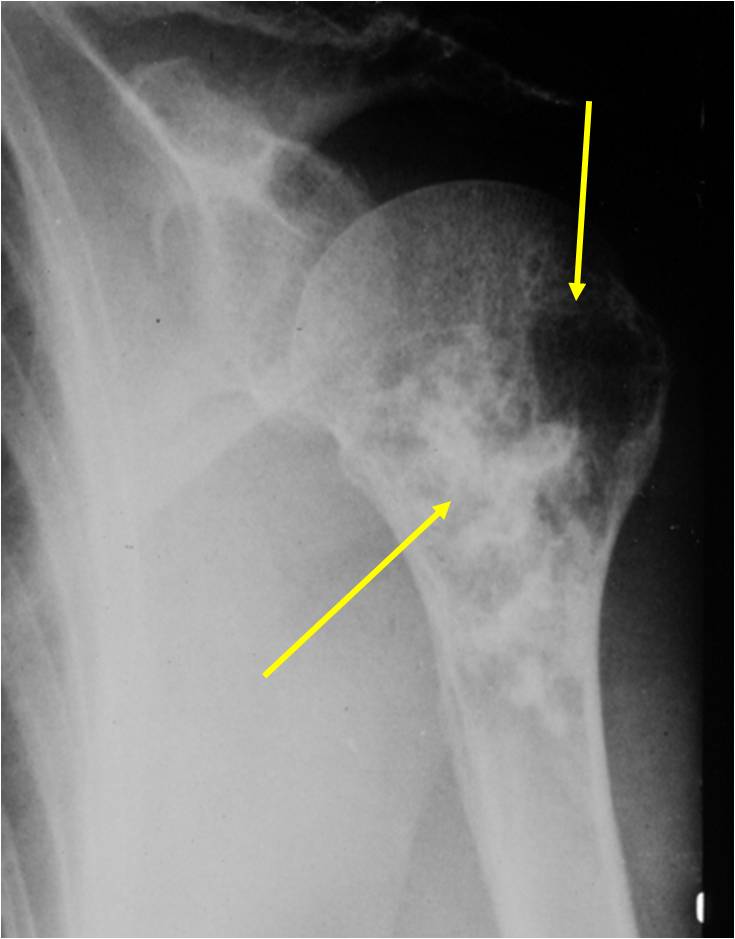

Radiology emulates pathology: Biphasic Tumor

- One region low grade chondrosarcoma

- Second more aggressive area with bone destruction, lysis of calcification, soft tissue mass

- Cortical permeation and a soft tissue mass in 70% of cases

Ill-defined, lytic intraosseous lesion

- Or extraosseous soft tissue mass

- Devoid of calcifications in continuity with lesions having the features of a cartilaginous tumor

Characteristically abrupt transition between chondroid tumor and dedifferentiated, lytic component

Bone may be expanded and adjacent cortex thickened

(Right Arrow)Aggressive Lytic Area (Dedifferentiated Sarcomatous Component) Cortical Destruction Soft Tissue Mass without Calcification